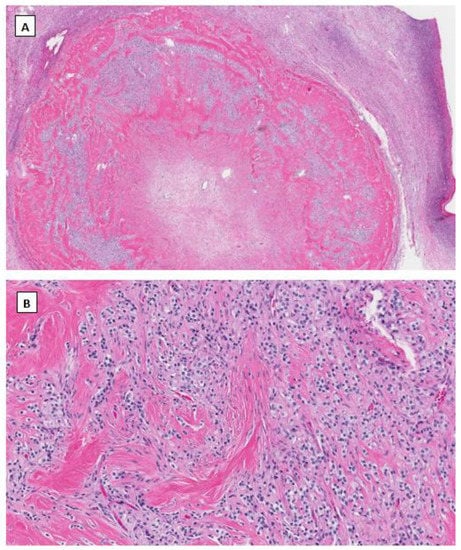

In 2009, Irving J.A. and Young R.H. described a novel and rare ovarian stromal neoplasm and named it the microcystic stromal tumor [36]. MCST presents as a unilateral solid tumor in middle-aged women without hormonal manifestations. Microscopically, most MCSTs show a distinctive triad of histologic features, including microcystic change, solid cellular regions, and extensive hyalinized fibrous stroma. Tumor cells have round to oval nuclei with inconspicuous nucleoli and the eosinophilic cytoplasm (Figure 2). Besides the unique extensive hyalinized fibrous stroma, the cytological features of these tumor cells are similar to those seen in ovarian SPPN. Immunohistochemical staining shows that tumor cells are positive for CD10, cyclin D1 and vimentin and variably positive for WT1 and CD56. Tumor cells are usually negative for cytokeratin, epithelial membrane antigen, synaptophysin, chromogranin, INSM1, inhibin, calretinin, and SF1. Maeda et al. first identified an aberrant β-catenin nuclear and cytoplasmic accumulation in MCST cells immunohistochemically [37]. Further molecular studies showed the identification of CTNNB1 mutations in exon 3, identical to that of SPPN, indicating dysregulation of the Wnt/β-catenin pathway in the pathogenesis of this neoplasm. Several other studies subsequently confirmed the above findings [38,39,40,41]. Furthermore, recent studies indicate that the incidence of MCST has increased among patients affected by familial adenomatous polyposis (FAP) due to APC germline mutations [42,43]. In both MCST cases reported by Liu et al. [43] and Lee et al. [42] there is no CTNNB1 mutation identified besides APC mutations. This has prompted a comprehensive molecular study by McCluggage’s group with the largest case series of MCST thus far [44]. Among 10 cases of MSCTs, they identified 8 cases harboring CTNNB1 mutations and 2 cases having APC mutations including one with germline APC mutation. CTNNB1 and APC mutations are mutually exclusive with no neoplasm exhibiting a mutation in both [44].

Figure 2.

Microcystic stromal tumor of the ovary. Tumor cells grow in delicate cords or solid sheets with blend cytology in a background of extensive hyalinized stromal fibrosis (H&E stain at 20× magnification for (A) and 200× magnification for (B)). Immunohistochemical staining demonstrates intense nuclear and cytoplasmic staining of Beta-catenin (C), intense nuclear with weak cytoplasmic staining of LEF-1 (D), and negative staining for SF1 (E) and inhibin (F). Immunostaining for β-catenin is at 200×, and for LEF-1, SF1 and inhibin are at 100× magnifications, respectively.